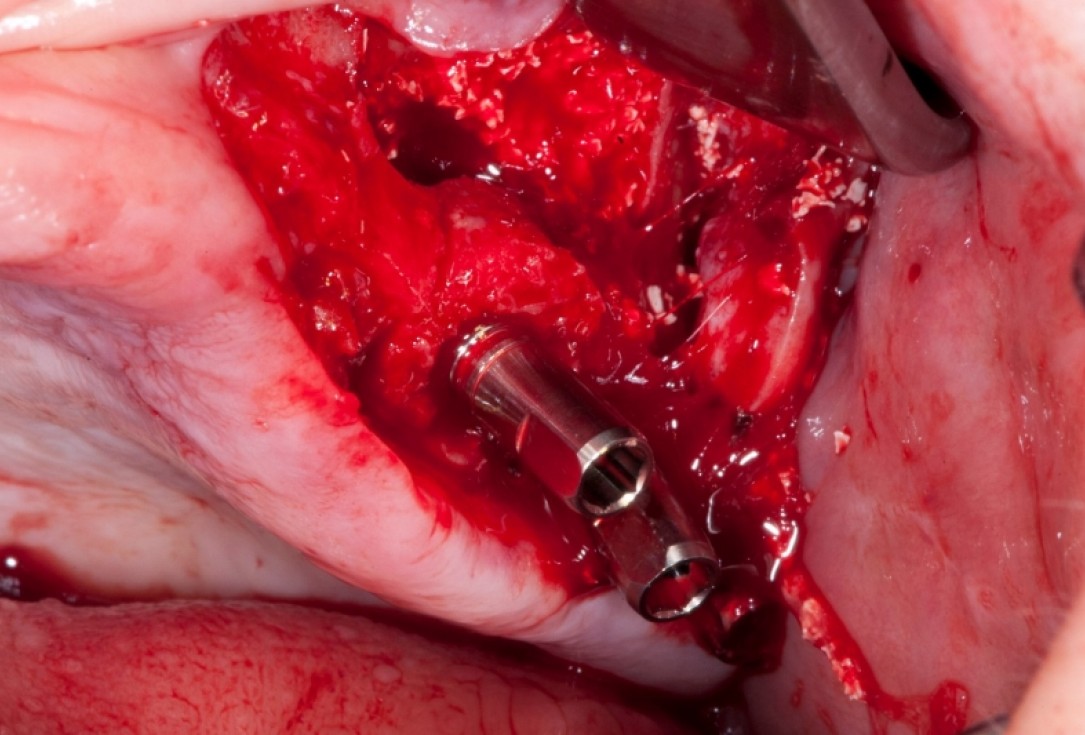

01/18 - Vertical augmentation: Preparation of ring bed in atrophic mandibula (third quadrant)